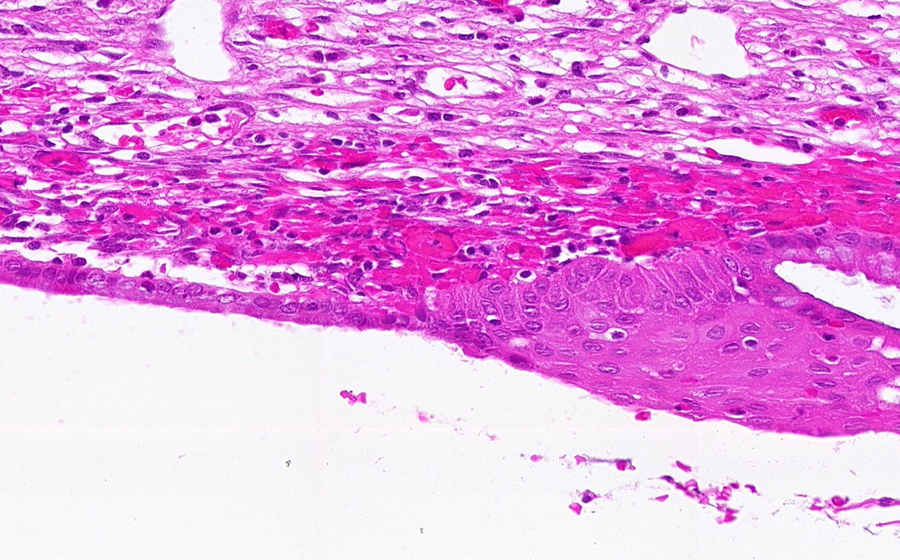

Slide 3: Chronic cervicitis and metaplasia

Histologic section of cervix from a patient with chronic cervicitis (click here to review normal tissue)

Image 3 - 100X

Slide 3 - Image 3